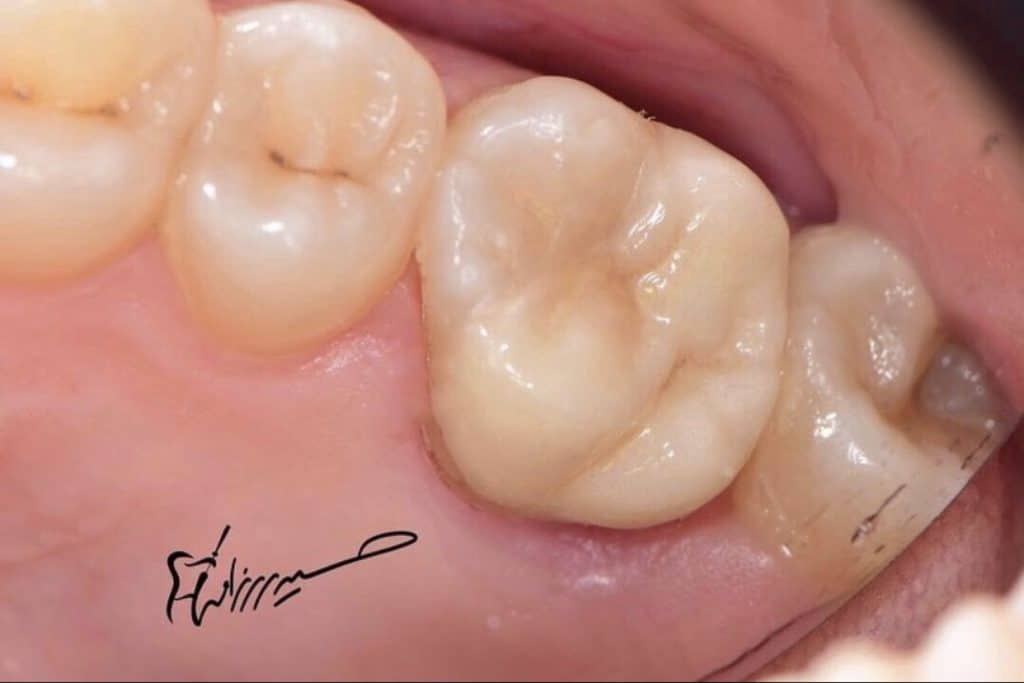

Initial situation